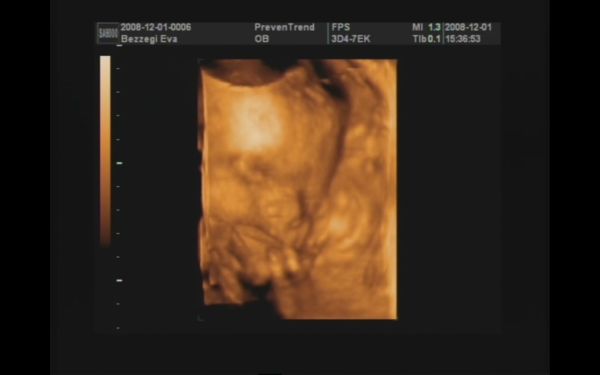

Majd jövök (ha a fiúktól egyszer visszaszerzem a gépet!!), addig is egy pár kép :D! 989 gramm a becsült súlya :shock: , két hete 776 gramm volt!!! Nagyon gyorsan gyarapszik ez a kis pöttömke! :D:D:D

Szerintem kommentálni nem kell :D!! Az integetős, mosolygós kép nekem nagyon tetszik!!